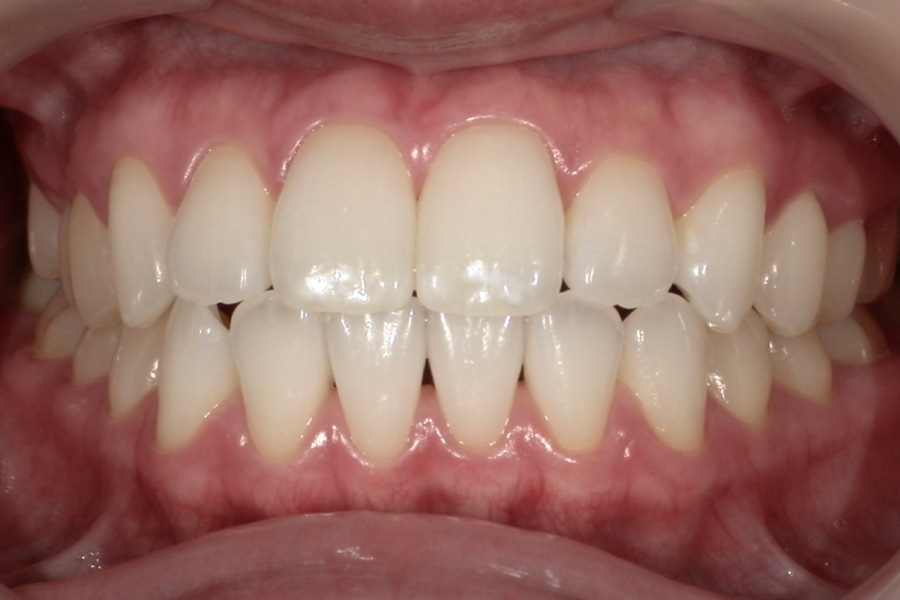

生涯、美味しく食べられる

豊かな人生を

“健口づくり”からサポートする

正しい診査診断、的確な治療をすることで、

歯だけでなく全身の健康に繋がります。

虫歯があるから削ったり悪くなったから抜くのではなく、まずは虫歯と歯周病が起きないようにより良い環境づくりをすること、そうすることによって歯を長く維持することが可能となります。